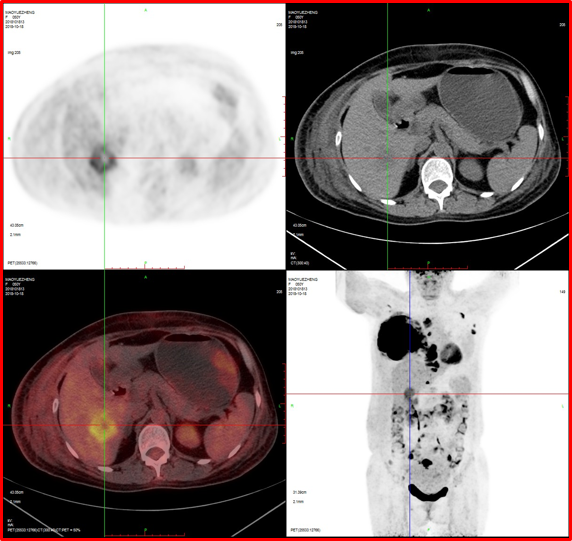

病例1:女性,50歲,乳腺腫瘤術前評估。

PET/CT檢查:

1、右側乳腺惡性腫瘤;

2、肝臟轉移。